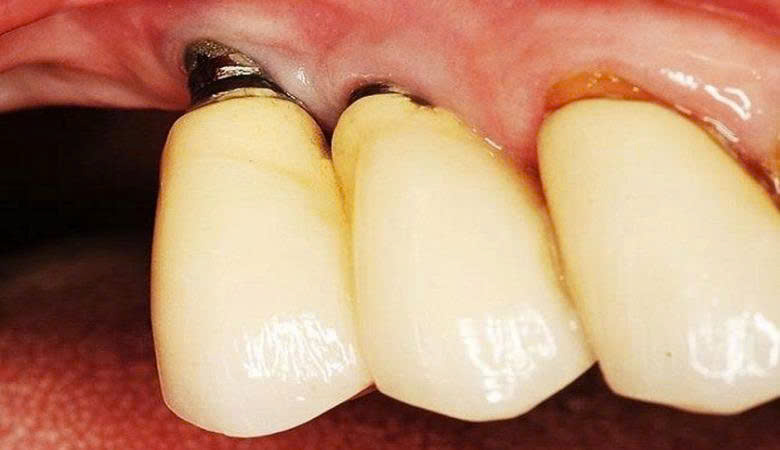

4. Trụ implant nứt hoặc gãy

Trụ implant không đạt tiêu chuẩn có thể gây kích ứng trong khoang miệng (Nguồn: Internet)

Vật liệu kém chất lượng không chịu được lực nhai, đặc biệt khi ăn đồ cứng, dễ khiến trụ bị nứt hoặc gãy. Khi đó, bệnh nhân phải phẫu thuật lại, tốn thêm chi phí, thời gian và đau đớn.